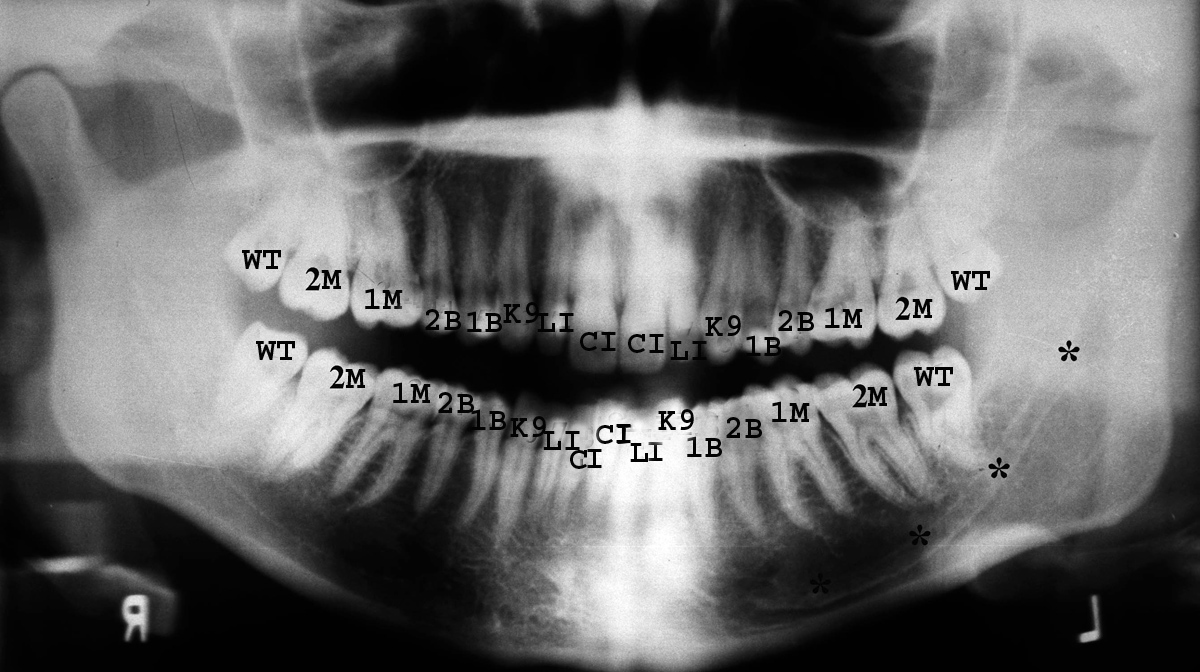

Tooth nomenclature and numbering are important for properly describing dental and mandibular lesions. Tooth nomenclature is based on tooth location and anatomic features (figure: tooth nomenclature). Central teeth refer to the two upper and two lower teeth in the most mesial, or medial, position of the mouth. Lateral teeth are the teeth directly lateral to the centrals. The centrals and laterals are also collectively referred to as the incisors. Cuspid teeth, or canines, are just lateral and posterior to the laterals and have only one cuspal or point. Bicuspids, or premolars, are located posterior to the cuspids and have two cuspals (points). Molars are posterior to the bicuspids and usually contain four cusps. The deciduous arch has four molars and no bicuspids. The permanent arch contains four bicuspids and six molars (figure: tooth nomenclature).

WT-wisdom tooth (3rd molar); 2M-second molar; 1M-first molar; 2B- second bicuspid (premolar); 1B-first bicuspid (premolar); K9-canine; LI-lateral incisor; CI-central incisor. The * marks the mandibular canal.